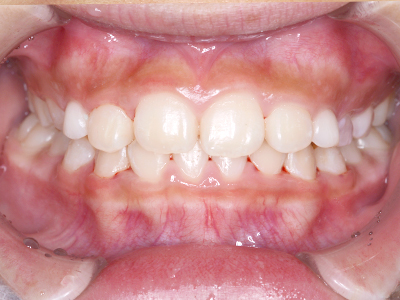

ないき歯科クリニックでは、これからあごが成長していくお子様や、歯並びが気になる成人の方など、さまざまな年代の方に対して矯正治療を行っています。

歯並びやかみ合わせを正しく整えると、笑顔や発音の自信につながり、むし歯・歯周病・口臭の予防にも役立ちます。

ないき歯科クリニックでは、上あごの成長不足を補い、鼻呼吸を獲得しつつ歯列を整え、将来のお口をより健康な状態にすることをゴールに定める矯正治療をおこなっています。